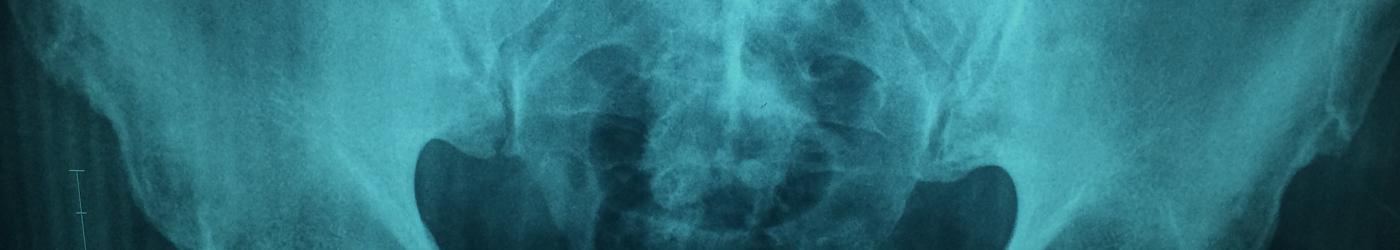

La urología es la especialidad médico-quirúrgica que se ocupa del estudio, diagnóstico y tratamiento de las patologías que afectan al aparato urinario y retroperitoneo de ambos sexos y al aparato reproductor masculino.

En nuestras consultas externas contamos con acreditados especialistas en urología, como el Dr. Gilberto Chechile y su equipo del Instituto Médico Tecnológico, que atienden visitas de esta especialidad de lunes a viernes de 9.00h a 21.00h y urgencias fuera del horario de visitas. Este equipo cuenta con un gran prestigio profesional, se han formado en la Fundación Puigvert, y se caracteriza por el uso de técnicas mínimamente invasivas, que no requieren cirugía abierta, y el uso de las últimas tecnologías como: